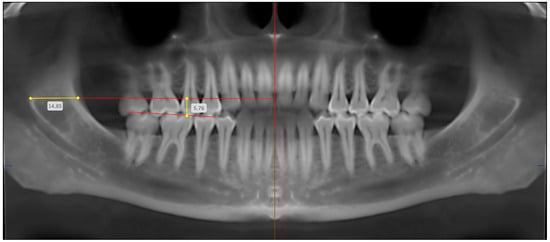

| Variable | Description | Radiographic Technique | Abbreviation Based on Anatomic Localization | |

|---|---|---|---|---|

| Right | Left | |||

| Anteroposterior position of mandibular foramen | Horizontal distance from anteroinferior border of mandibular foramen to anterior border of mandibular ramus | OPG | MF-AP-OPG (Right) | MF-AP-OPG (Left) |

| CBCT | MF-AP-CBCT (Right) | MF-AP-CBCT (Left) | ||

| Superoinferior position of mandibular foramen | Vertical distance from anteroinferior border of mandibular foramen to mandibular occlusal plane (at level of mesial cusp of first molar) | OPG | MF-SI-OPG (Right) | MF-SI-OPG (Left) |

| CBCT | MF-SI-CBCT (Right) | MF-SI-CBCT (Left) | ||